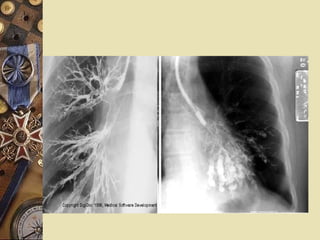

Evaluation 1.Roentgenographic studies Bronchography:  (traditional gold standard)

Evaluation 1.Roentgenographic studiesBronchography: (traditional gold standard)